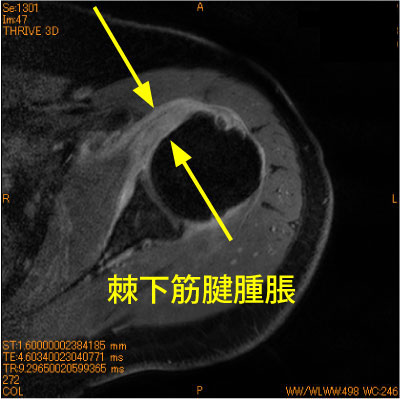

60代女性、長時間のマッサージの疼痛肩、造影後、脂肪抑制T1強調画像である。肩甲下筋の著明な腫脹と造影を認めている。

腱挫傷であるが、契機と肩甲下筋腱の損傷が稀である。

同部の腫脹は烏口突起との擦れの悪循環をつくる。

![]() Axial T1 造影後 脂肪抑制 |